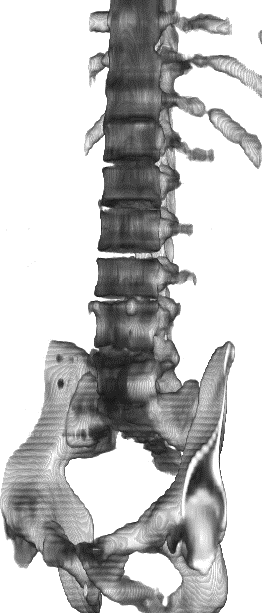

Figure 1: 3D renderings of bones from CT slice interpolation results. Bicubical interpolation (a) from sparsely sampled CT volume, with highly unrealistic distortions. Methods (b) and (c) improve the image quality; however, they are still under-resolved as is evident on the spinal column. SAINT (d) resolves details much better on the spinal column.

CT image acquisition is much faster than MRI; however, due to the high cost of keeping complete 3D volumes in memory and print, typically only necessary number of slices are stored. As a result, most medical imaging volumes are anisotropic, with high within-slice resolution and low between-slice resolution. The inconsistent resolution leads to a range of issues, from unpleasant viewing experience to difficulties in developing robust analysis algorithms. Currently, many datasets [9, 19, 1] use affine transforms to equalize voxel spacing between volumes, which may introduce significant distortions to the original data, as shown in Fig. 1(a). Therefore, methods for some analysis tasks, e.g. lesion segmentation, have to resort to intricate algorithms to take into account of the change in resolution[18, 22, 16]. As such, an accurate and reliable 3D SISR method to upsample the low between-slice resolution, which we refer to as the slice interpolation task, is much needed.

SAINT then introduces a Residual-Fusion Network (RFN) that eliminates the inconsistencies resulting from applying AMI (which addresses images in 2D) to 3D CT images, and incorporates information from the third axis for improved modeling of 3D context. Benefited by the effective interpolation of AMI, RFN is lightweight and converges quickly. Combining AMI and RFN, SAINT not only significantly resolves the memory bottleneck at inference time, allowing for deeper and wider networks for 3D SISR, but also provides improved performance, as shown in Fig. 1.